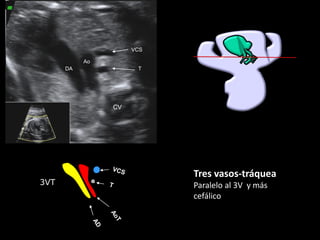

3VT

Tres vasos-tráquea

Paralelo al 3V y más

cefálico

▪ La Ao transversa y el

ductus son

aproximadamente del

mismo tamaño

▪ La VCS se ve en sección

transversal a la derecha

de la Ao

▪ La tráquea está a la

derecha de los grandes

vasos, por debajo de la

VCS

▪ No hay vasos accesorios

▪ Por Doppler color los dos

vasos arteriales tienen

flujo anterógrado